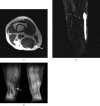

Intratendinous ganglion cyst is a very rare lesion with an unknown aetiology that originates within the tendon. We encountered a case of 43-year-old woman who complained of a palpable, non-tender mass in the thigh with increasing swelling. An intratendinous ganglion cyst in the semimembranosus tendon of the lower extremity was diagnosed and located by ultrasound and MRI. Nine months after a surgical excision, there were recurrent ganglion cysts along the semimembranosus tendon. We describe this case with a review of the relevant literature.